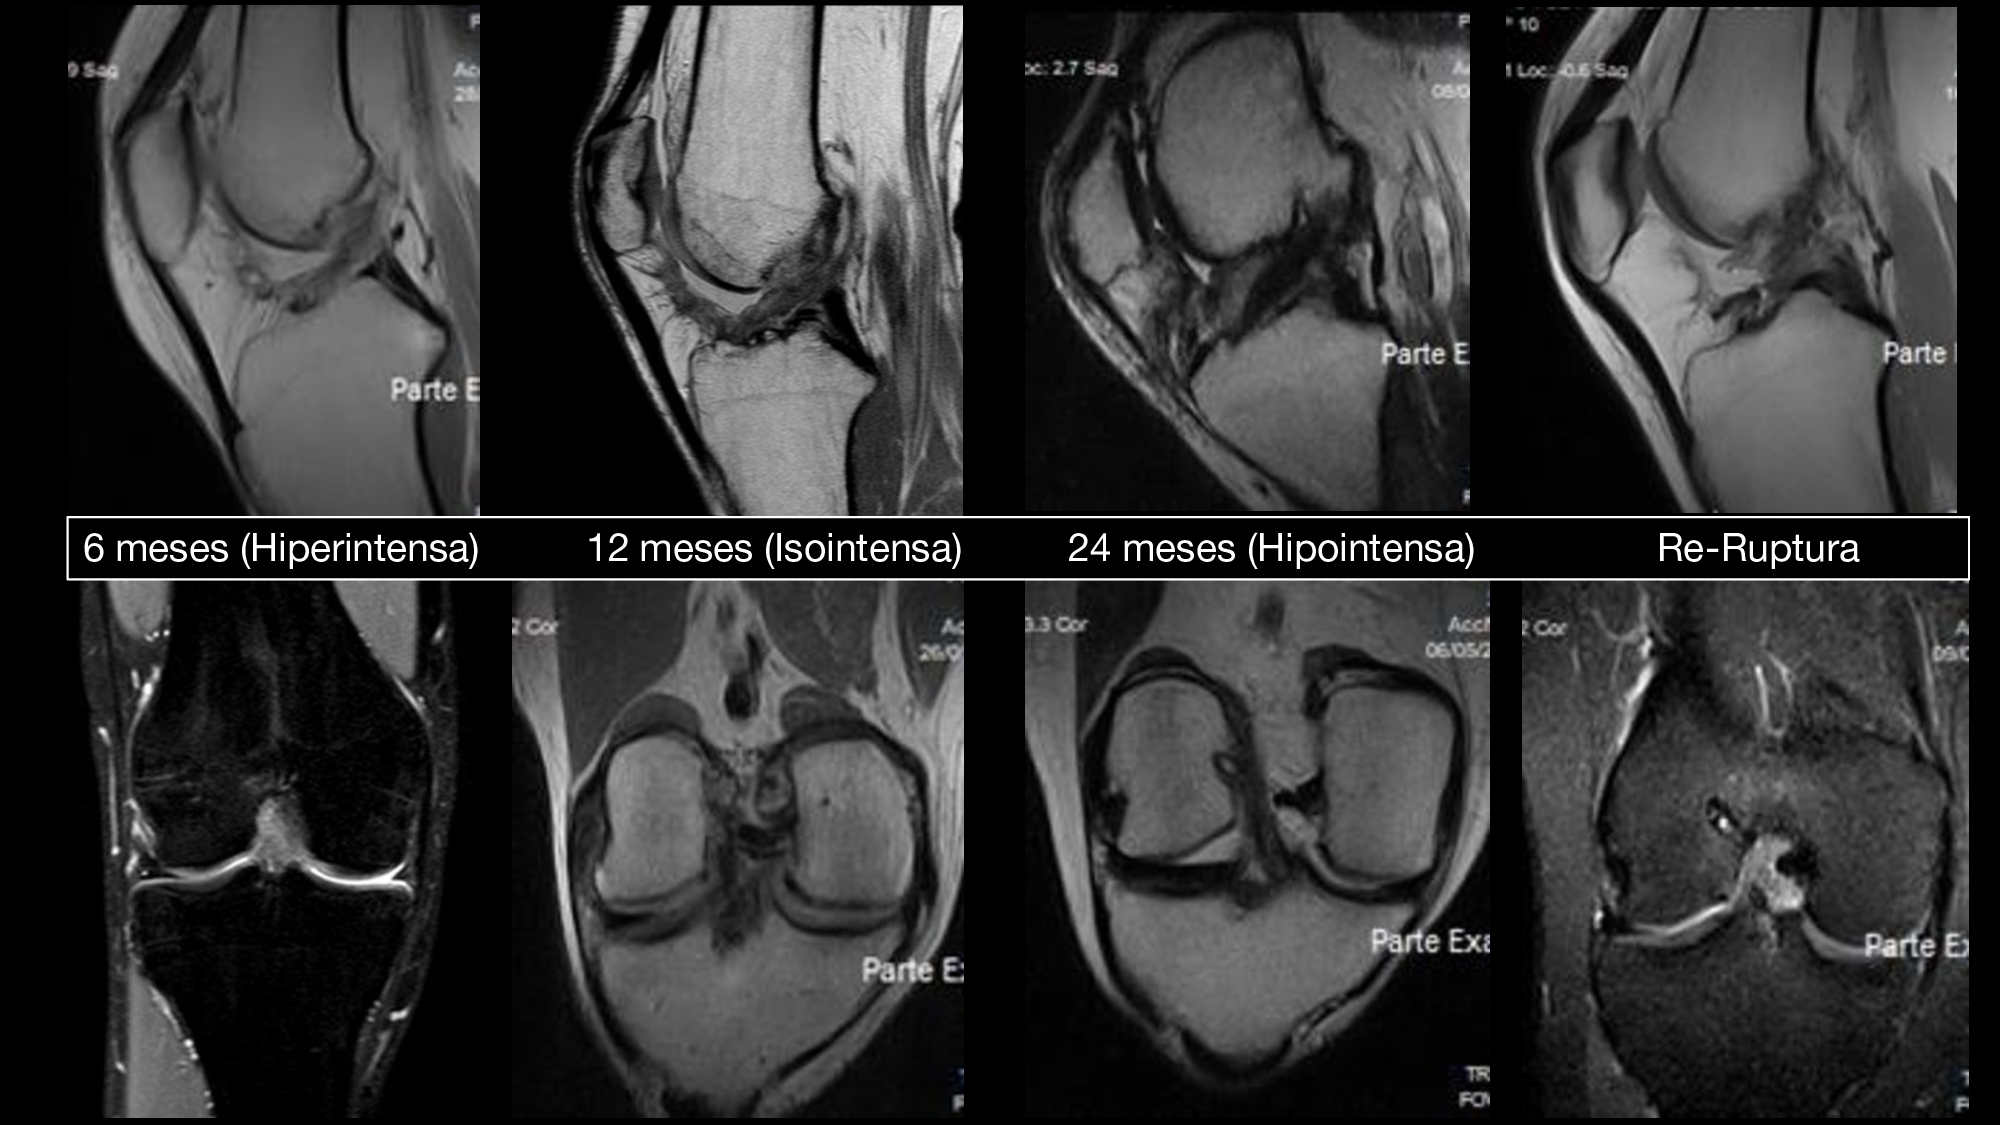

25_“Evaluación de Resonancia magnética en reparación primaria del LCA”

Dres. Jorge Pablo Batista - Jorge Chahla - Lucia Cangiano - Agustín Quesada - Rodrigo Maestu - Matías Luna (Ciudad de Buenos Aires)